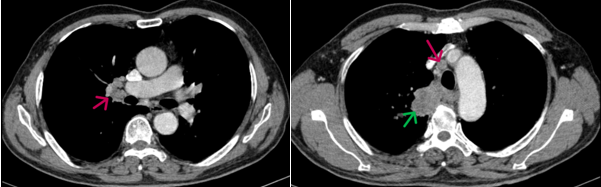

- Chụp cắt lớp vi tính lồng ngực (20/08/2024): Thùy trên phổi phải có khối đặc kích thước ~ 67x39mm, bờ không đều, ngấm thuốc sau tiêm không đồng nhất, dày tổ chức kẽ dạng lưới và kính mờ xung quanh, lân cận có nốt kính mờ đường kính ~5mm, phát triển vào trung thất, đẩy khí quản và thực quản lệch trái, có phần không rõ ranh giới với thành thực quản đoạn ngang mức. Phổi trái giãn phế nang trung tâm tiểu thùy và cạnh vách chủ yếu thùy trên. Trung thất, rốn phổi phải có vài hạch kích thước ~13x17mm, ngấm thuốc không đều sau tiêm.

Hình 2. Hình ảnh hạch rốn phổi và hạch trung thất (mũi tên đỏ) kích thước khoảng 13x17mm

+ Chụp cắt lớp vi tính lồng ngực (16/12/2024): Hình ảnh cấu trúc dạng hang thùy trên phổi phải, kích thước ~36x22x44mm, bờ không đều, thành dày không đều, ngấm thuốc không đồng nhất sau tiêm. Hạch trung thất và rốn phổi phải.

Hình 6. Khối u trước và sau điều trị (mũi tên xanh), sau điều trị kích thước khối u giảm còn khoảng 36x22x44mm

Hình 7. Hạch trung thất trước và sau điều trị (mũi tên xanh), kích thước hạch sau điều trị giảm xuống còn dưới 10mm đường kính trục ngắn.

*Kết luận: Ca lâm sàng trên cho thấy một trường hợp bệnh nhân nam lớn tuổi, chỉ số toàn trạng (Performance Status - PS) 1, vào viện với tình trạng khó thở và đau ngực nhiều, được chẩn đoán Ung thư phổi không tế bào nhỏ giai đoạn IIIB. Sau 4 chu kỳ hóa trị liệu với phác đồ Docetaxel - Carboplatin, bệnh nhân đạt được đáp ứng bệnh một phần, khối u giảm khoảng 50% kích thước so với trước khi điều trị, kích thước hạch trung thất giảm và nhiều hạch không còn nhìn thấy trên phim chụp cắt lớp vi tính. Sau điều trị bệnh nhân hết các triệu chứng lâm sàng, thể trạng được cải thiện và sinh hoạt trở lại bình thường. Bệnh nhân tiếp tục được đánh giá lên kế hoạch điều trị tiếp theo.